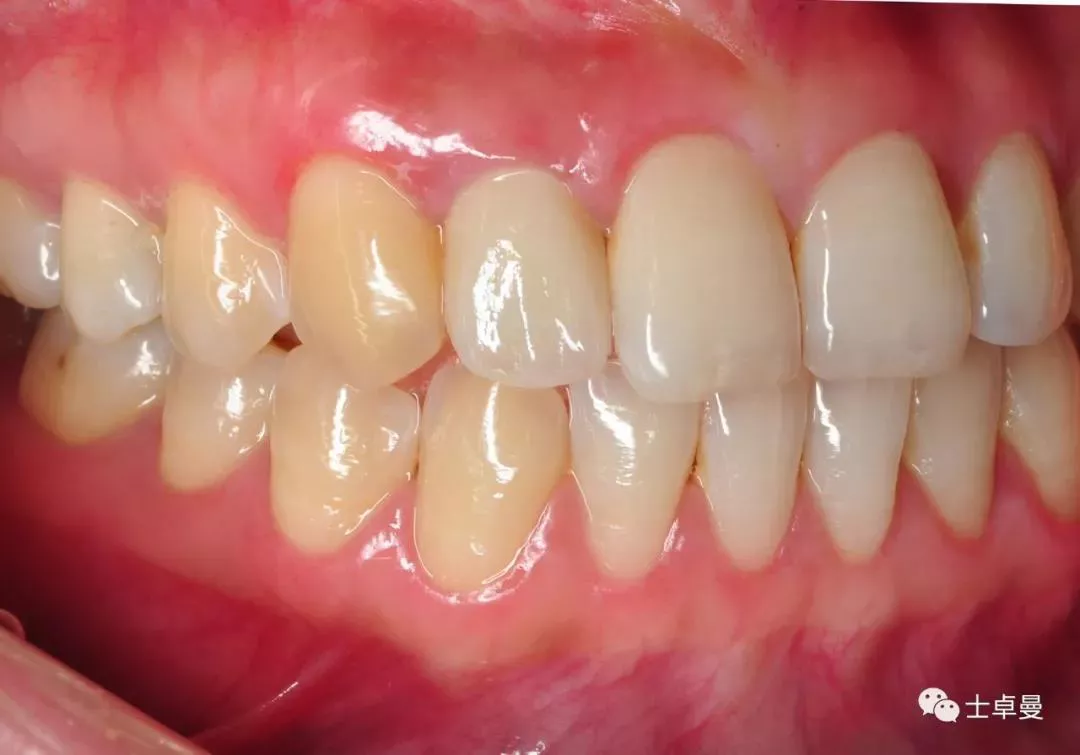

龈缘曲线高度协调一致

个性化取模

口内完成修复当日

完成修复一年后复查

修复后3年复查